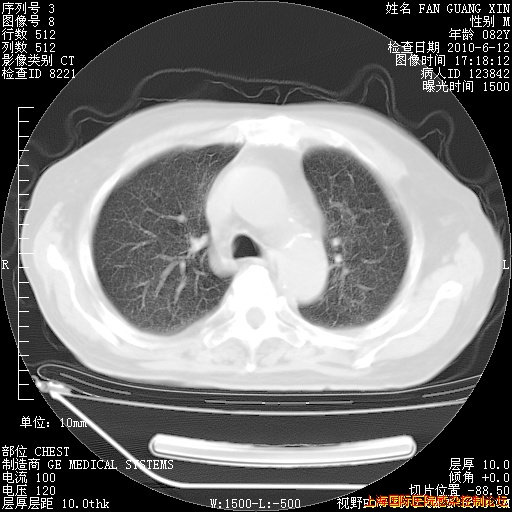

补发6月12日肺部CT肺窗

6月12日肺窗

整整相隔30天的肺部CT好像有所好转啊。甲强龙减量第3天,需要观察体温。